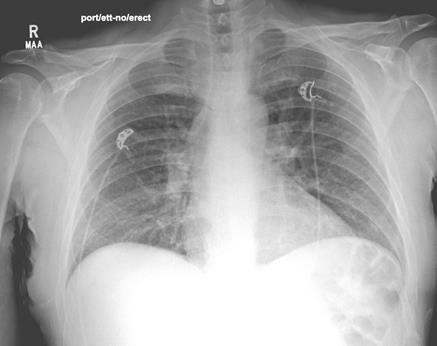

Meanwhile, intraoperative wound cultures grew Staphylococcus aureus and Gram-negative rods, and SARS-COV-2 PCR was negative. Per infectious disease recommendations, we discontinued vancomycin and clindamycin, while continuing piperacillin-tazobactam and levofloxacin. Later, however, due to suspected drug-induced pneumonitis, we also discontinued the piperacillin-tazobactam. The patient's respiratory status is markedly improved the following day, and he discontinued BiPAP on admission day 6. Repeat chest X-rays taken on day 7 (see photo below) showed spontaneous resolution of his systemic symptoms. The following day, the patient underwent right foot TMA with primary closure. Upon discharge the patient had prescriptions for oral levofloxacin and newly added metronidazole for a 10-day course. At 12-month follow up, the patient has complete healing of the right TMA site without any systemic complications.